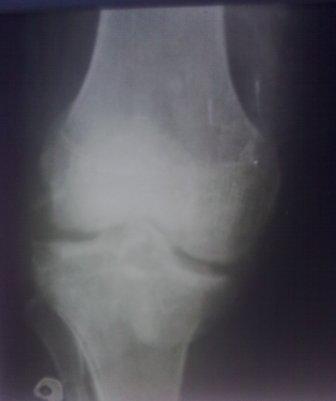

Здравствуйте уважаемые коллеги!Сегодня обратился больной 35л. Травму получил 3 мес.назад, упал в яму, лечился в отдаленном районе гипсовой повязкой, 1 месяц назад гипс сняли , и больной начал ходить с нагрузкой, постепенно появилась деформация коленного сустава, неустойчивость и боли. Локально: деформация коленного сустава, голень смещена кзади- типа подвывиха, разгибание 170гр. Сгибание 150гр.симптомов повреждение коллатеральных и крестообразных связок определить не удается из-за боли и контрактуры. Первичных снимков пока нет, обещали принести, имеется снимки через 2 месяца после травмы без гипса, недельной давности снимки в прямой проекции и К Т. Похоже, что импрессия переднемедиальной части внутреннего мыщелка б/берцовой кости, отрыв межмыщелкового возвышения.

На снимке типичный перелом медиального тибиал плато с передним смещением (подвывих) по Schatzker IV. Консервативное лечение без медиальной опоры не может удержать деформирующие силы, и из-за вторичного смещения мыщелка конечность смещается в варус. Кроме передних смещений еще встречаются сложные фронтальные варианты переломов, и тогда голень подвывихивается кпереди.

А в данном случае мыщелок сросся со смещением кпереди и ротирован. За счет интактной наружной колонны опороспособность конечности сохранена, но остается варус и экстензия конечности. Для предоперационного расчета необходимо сделать на всю длину конечности рентгенограмму, а в остром периоде КТ и 3-мерный снимок помогут лучше ориентироваться в характере перелома.